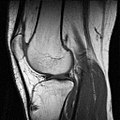

MRT-Kniegelenksaufnahme (sagittales Schnittbild) -